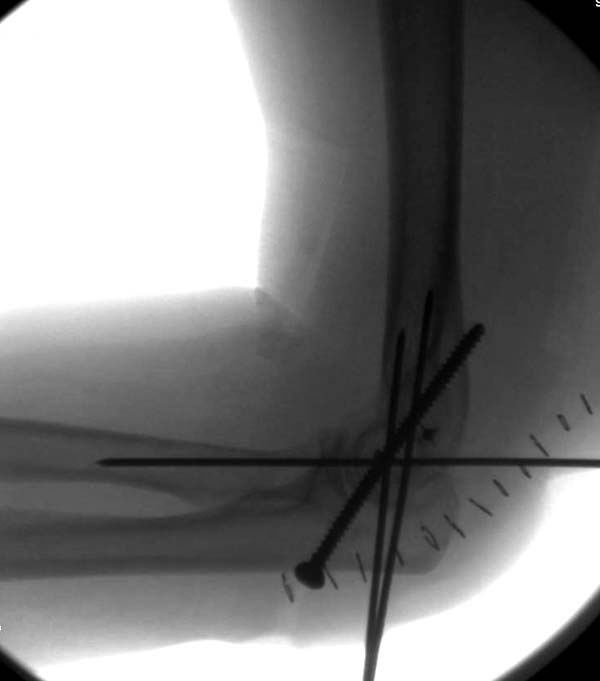

Снимки: 1-2 вывих, 4-5 вторичное смещение в гипсе, реконструкция

латеральной связки и капсулы 13-14, повторный вывих после реконструкции,

перевод в наш центр; 18-21 временная фиксация, 22-25 трансартикулярная

фиксация и нестабильная головка фиксирована спицами, 29-30 амбулаторно,

Имя     : 18 Elbow dislocation closed reduction SLU 3.JPG

Тип     : image/jpeg

Размер  : 24892 байтов

Описание: отсутствует

Url     : http://weborto.net:8080/pipermail/ortho/attachments/20131212/4b05a6a3/attachment-0008.jpeg